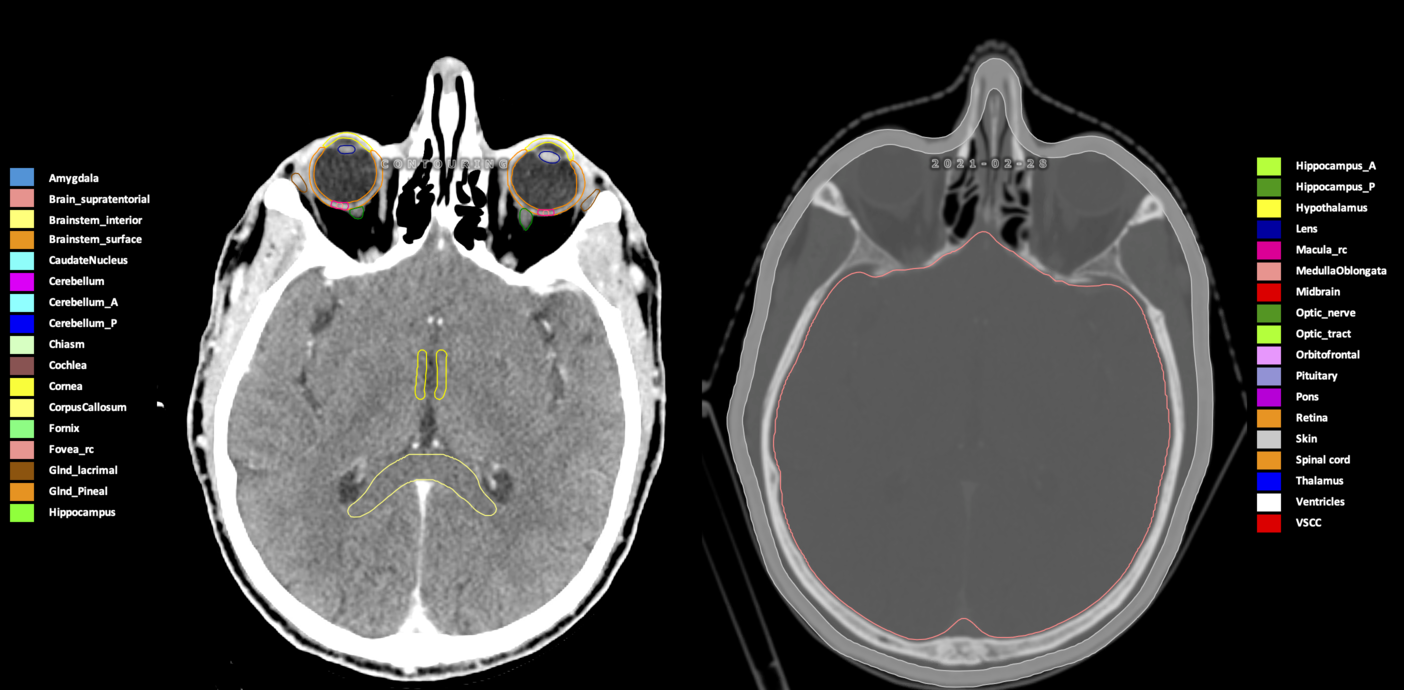

Included are all OARs known to be relevant for radiation-induced toxicity in neuro-oncology: brain, brainstem (midbrain, pons, medulla oblongata), chiasm, cerebellum (anterior & posterior), cochlea, cornea, hippocampus (anterior & posterior), hypothalamus, lens, lacrimal gland, optic nerve, pituitary, skin, and vestibular & semicircular canals. To further facilitate research on cognition, vision and radiological changes after irradiation of the brain, potential clinically-relevant OARs are included: amygdala, caudate nucleus, cerebellum (anterior & posterior), corpus callosum, fornix, macula, optic tract, orbitofrontal cortex, periventricular space (PVS), pineal gland, and thalamus.

Three-dimensional delineation of the 25 consensus OARs for neuro-oncology are shown on CT (WW/WL 120/40, 3000/600), 3T MR images, (T1Gd, T2FLAIR 1mm) and 7T MR (MP2RAGE 0.7 mm). All are presented in transversal, sagittal and coronal view.